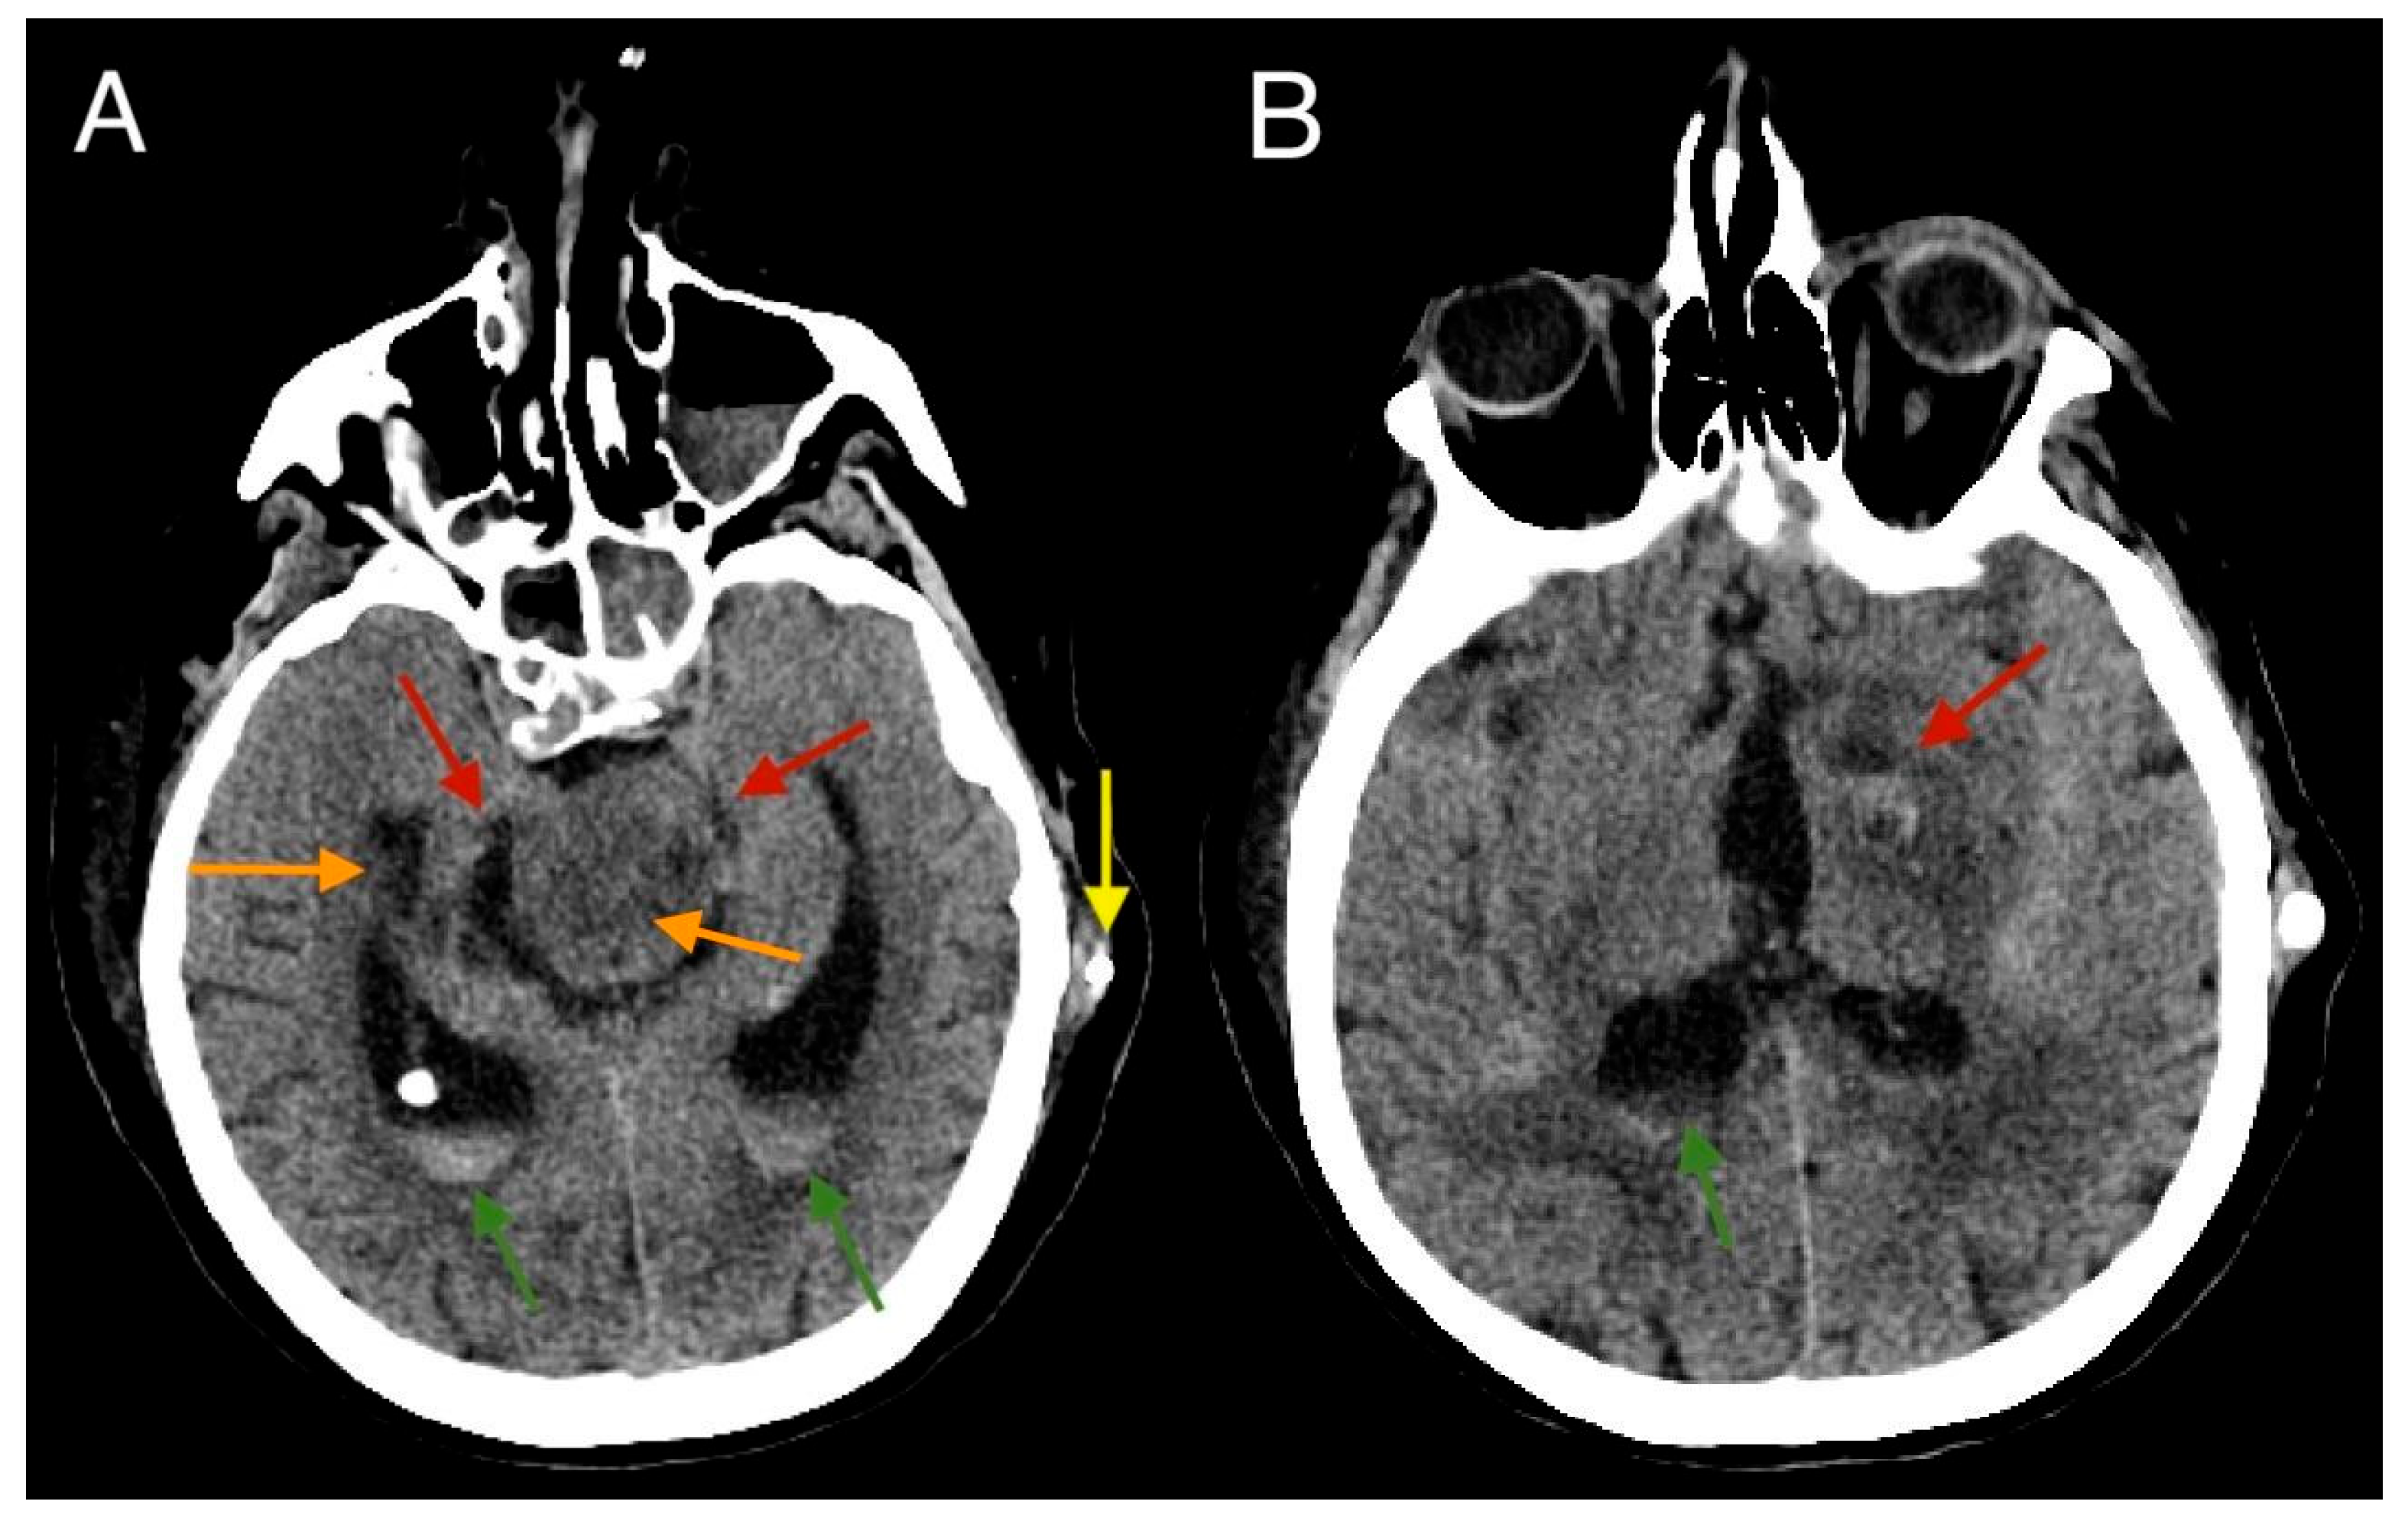

2. Case Report